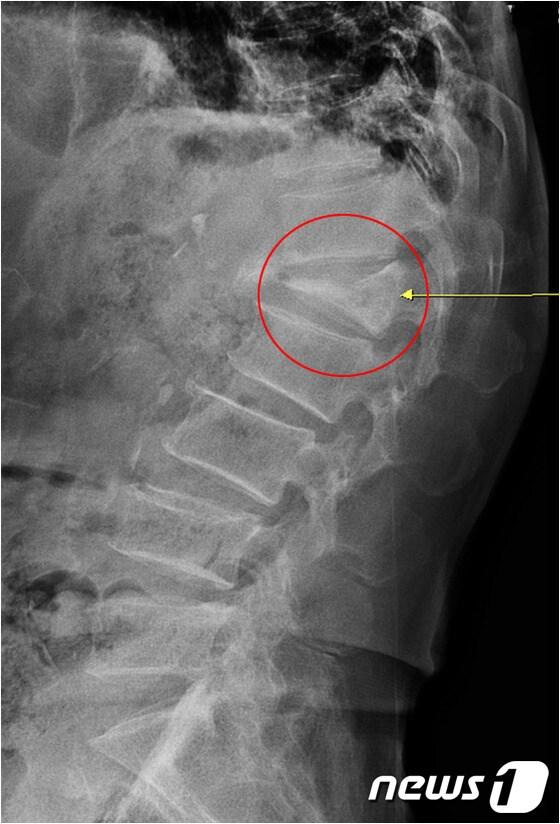

압박골절로 인해 주저앉은 척추체ⓒ News1